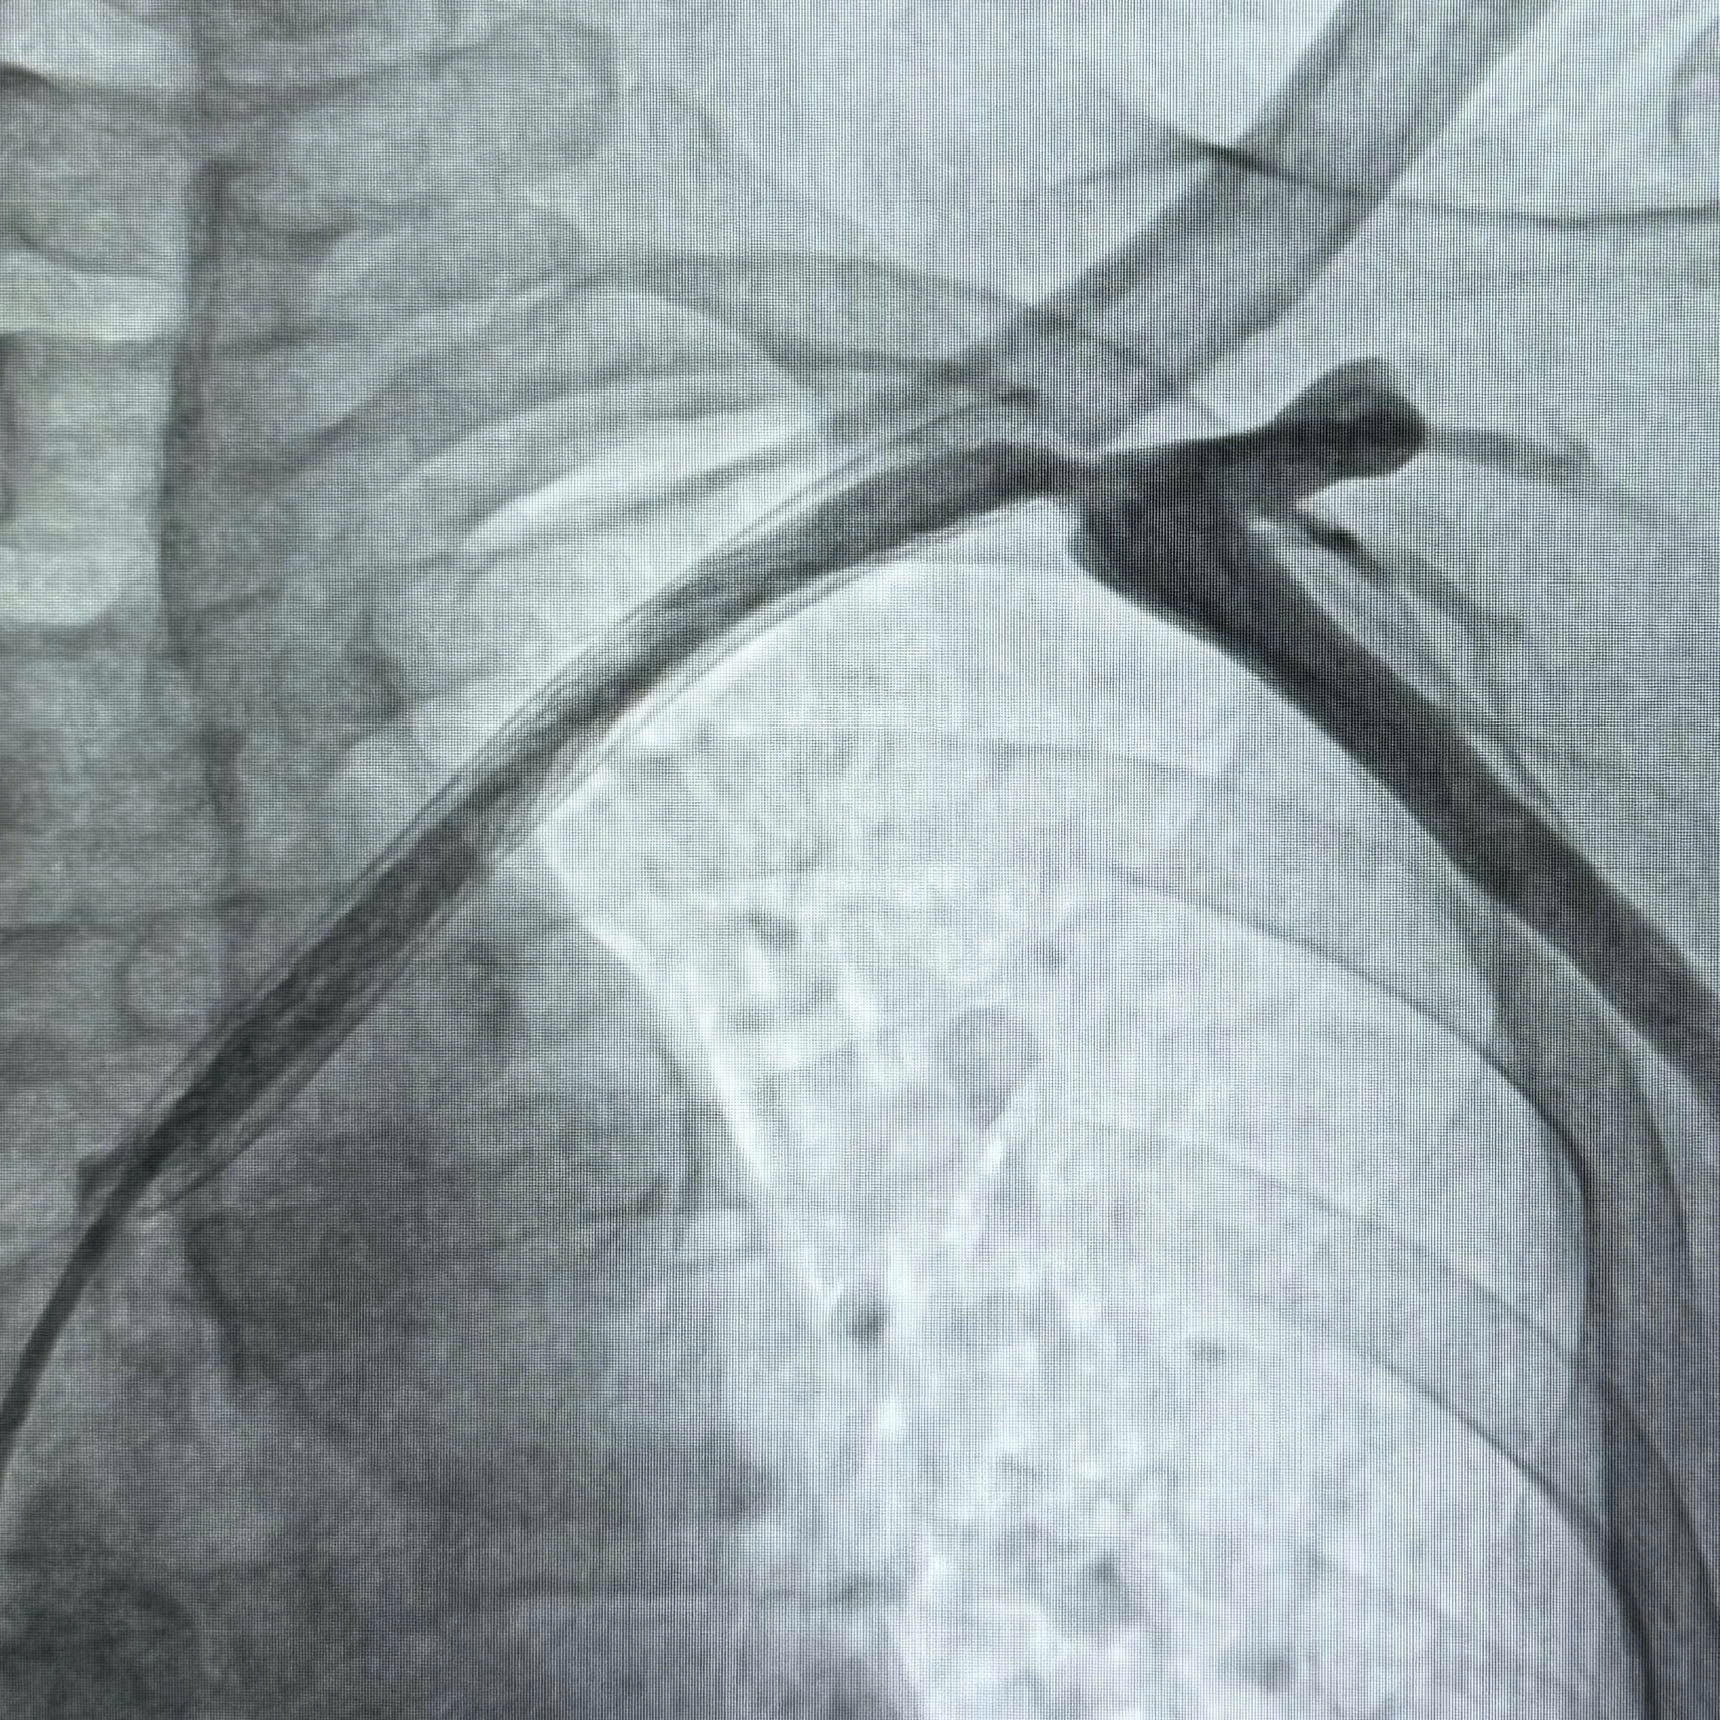

Ngày 1/4/2026, ekip can thiệp gồm TS.BS Hoàng Phương, BS Phạm Tấn Hoàng Long cùng các kỹ thuật viên đã tiến hành thủ thuật. Dưới hệ thống chụp mạch số hóa xóa nền DSA hiện đại của hãng Siemens, ekip đã thực hiện can thiệp qua da chỉ với gây tê tại chỗ. Sau gần 2 giờ đồng hồ tập trung cao độ, hai vị trí tắc hẹp hoàn toàn đã được khai thông, tái tạo dòng chảy thông suốt.

Kết quả sau can thiệp mang lại sự thay đổi kỳ diệu. Ngay trên bàn mổ, bệnh nhân đã giảm đau đến 50%. Sau một tuần điều trị, cánh tay ông P. đã xẹp hẳn, cử động tự do và ông đã có thể ăn ngủ tốt trở lại.

Dòng chảy được tái thông...